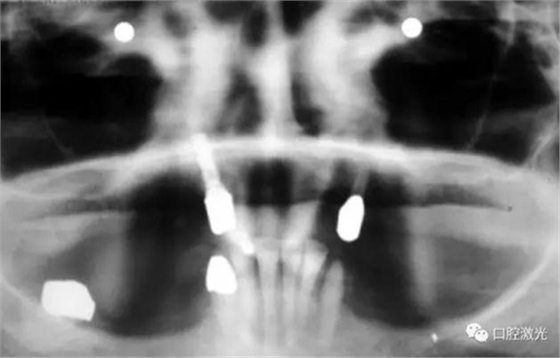

治療十年以上恢復情況

如今,種植體周圍炎的治療完成已經(jīng)過去了10多年,上顎義齒的狀況沒有再出現(xiàn)問題。種植體周圍組織基本健康。

如果不及時治療,種植體周圍炎會導致種植體失敗。在本例中,種植體的缺失將給患者的生活帶來嚴重的不便。得益于激光對種植體周圍病變組織的殺菌治療,使得發(fā)炎組織得到有效控制,同時使得周圍軟、硬組織得到了很好的保持和很快的恢復。